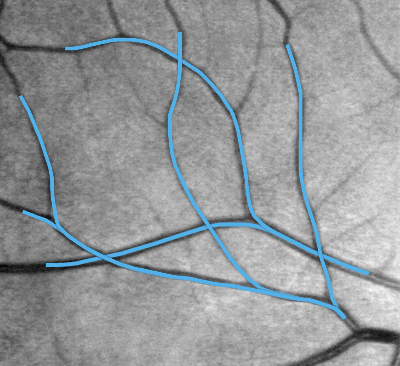

В частности, задача поиска выделяющихся кривых возникает в анализе медицинских изображений при поиске кровеносных сосудов на фото сетчатки глаза человека, см. Рис. 3. Типичные проблемы для промышленных систем трассировки возникают в ситуациях, когда сосуды на фото пересекаются. Решение этой проблемы достигается путем поднятия изображения в расширенное пространство позиций и направлений. Метод трассировки сосудов с помощью СР кратчайших на предложен в [11].

Недостатком СР модели является наличие точек возврата. Такие кривые нежелательны в задаче трассировки сосудов. Ограничение управления на полукруг устраняет этот недостаток. При этом точки возврата становятся точками поворота на месте. Возникновение точки поворота типично наблюдается в местах ветвления сосудов. Более подробно с результатами трассировки сосудов с помощью оптимальных траекторий на с управлением в полукруге можно ознакомиться в [28].